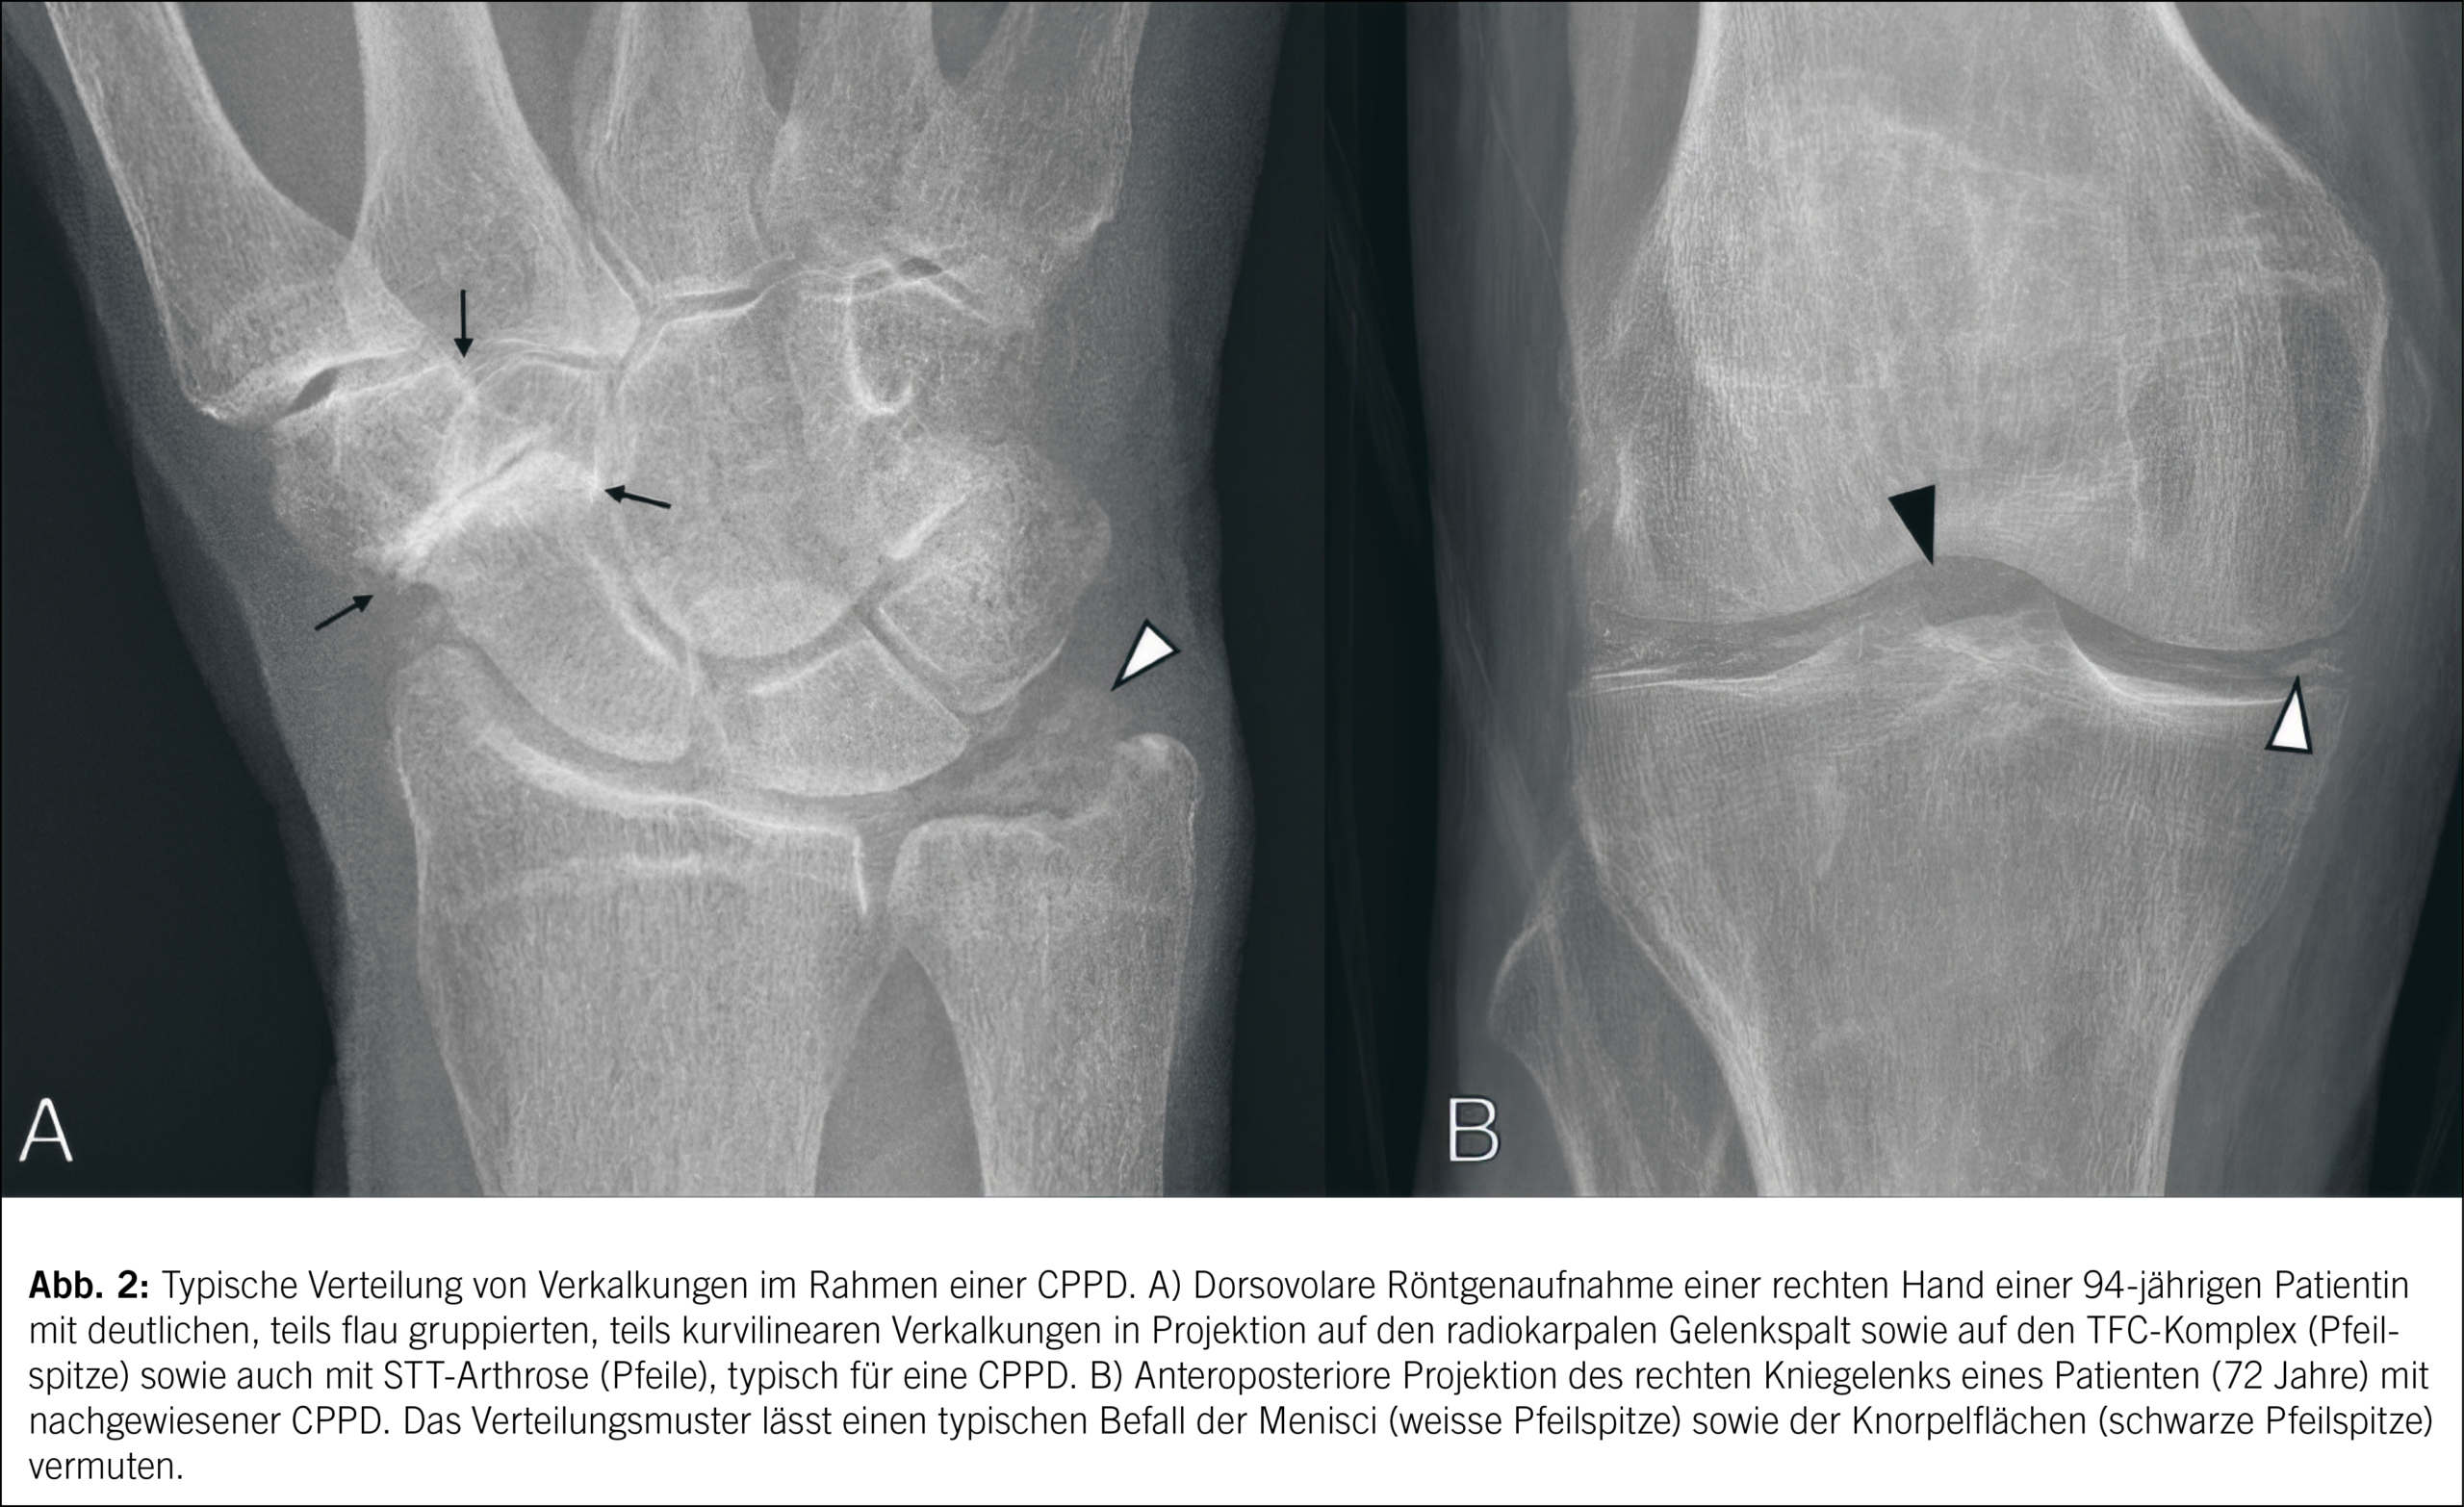

Diese Aufnahmen können Verkalkungen im Knorpel (Chondrocalcinose) und gelegentlich auch in den Weichteilen sichtbar machen. Chondrocalcinose zeigt sich typischerweise als lineare Verkalkungen im hyalinen Knorpel und im fibrillären Knorpel der Menisci und Bandscheiben. Häufig sind Kniegelenke, Handgelenke und Symphyse betroffen. Als weiteres diagnostisches Zeichen sprechen Knorpelschäden und knöcherne Veränderungen wie subchondrale Zysten und Osteophyten, aber auch subchondrale Sklerosen und eine eher diffuse Verengung des Gelenkraums für eine CPPD. Erosionen, sofern vorhanden, sind im Gegensatz in der Regel weniger klar definiert (Abb. 2).

Im Ultraschall hingegen äussern sich als Pendant zu den konventionell radiologischen Verkalkungen echogene, lineare Strukturen im Knorpel, die oft parallel zur Oberfläche des Knorpels verlaufen. Das wichtigste Ultraschallmerkmal ist somit das Vorhandensein linearer oder punktförmiger echoreicher Signale im hyalinen Knorpel und Faserknorpel, bekannt als «Ultraschall-Chondrocalcinose». Die Sonographie kann auch kristallinduzierte Synovitiden und Bursitiden aufdecken. Die primäre Rolle der Computertomographie besteht in der Darstellung von Verkalkungen bei sekundär arthrotischen Gelenken, für welche ein chirurgischer Gelenkersatz geplant ist. Hinzu ist auch bei der CPPD die DECT hilfreich, um das Vorhandensein anderer Kristalle wie Harnsäurekristalle zu differenzieren. Ein typisches MRT-Merkmal bei CPPD ist eine niedrige bis mittlere Signalintensität von Verkalkungen in T1- und T2-gewichteten Sequenzen. Die MRT hilft insbesondere bei der Beurteilung von CPPD im Zusammenhang mit Knorpelschäden und anderen differenzialdiagnostischen intraartikulären Pathologien.